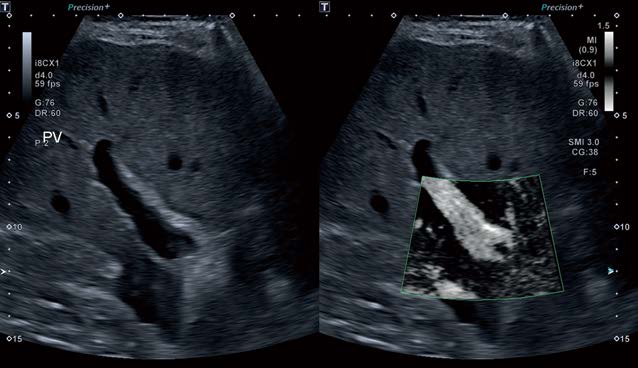

Малюнок 1 При ретельному дослідженні ворітної вени видно деякий залишковий тромб довжиною 34,8 мм

Малюнок 2 mSMI використовувався для оцінки прохідності ворітної вени. Тромб окреслюють за допомогою Caliper.

Цей випадок підкреслює дану технологію прибираючи наявний в судинах печінки шум, при цьому залишивши відповідні відлуння від тромбозу. Superb Micro-vascular Imaging (SMI) розкриває весь свій потенціал на Aplio i800 і є технологією, розробленою для оцінки повільного кровотоку. Однак вона також дає велику інформативність у спостереженні за зонами високошвидкісного потоку, особливо коли важлива просторова роздільна здатність. Монохромний SMI (mSMI) використовувався в цьому випадку для візуалізації глибокої судинної мережі печінки та показав справжній розмір просвіту без зафарбовування кольорових пікселів Доплера.

Існує ряд кольорових карт, які можна використовувати для відображення потоку. mSMI показує зображення в B-режимі з кольоровою рамкою, що перекриває область інтересу. У цій зоні інтересу зображення в режимі B прибирається, щоб забезпечити ще більшу чутливість візуалізації потоку, оскільки око не відволікається на пікселі відтінків сірого в режимі B. mSMI відображається у подвійному вікні з еталонним зображенням у B-режимі, що відображається поруч із кольоровим.

Малюнок 4 mSMI з подвійним вікном дозволяє відображати еталонне зображення в режимі B поруч із зображенням mSMI – обидва зображення активні одночасно.